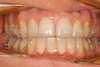

Vues pendant le traitement